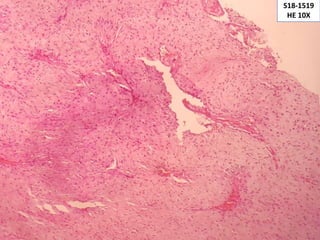

S18-1519

HE 10X

Características microscópicas

Se caracterizan por

presentar proliferación

estroma fibrocolagenosa

con una mezcla de

espacios vasculares de

variable tamaño

El componente vascular

esta formado de delgadas

paredes con pequeños a

grandes vasos que difieren

en su apariencia ya sean

estas estrelladas o cuernos

de ciervo, además tejido

fribroso.

Las áreas centrales del

tumor pueden ser

hipovasculares

• #23 Angiofibroma nasofaríngeo compuesto por una mezcla de fibras colágenas en el estroma y espacios vasculares de variable tamaño con una pared delgada

• #24 Menos conspicuo debido a la marcada compresión causada por el estroma fibrocolageno, nótese que las paredes vasculares presentan una incompleta o ausente capa muscular